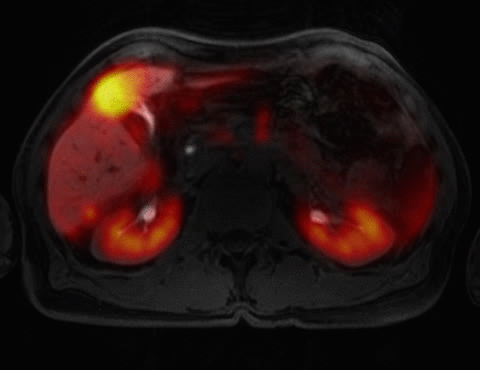

Imaging of Neuroendocrine Tumors

We have been evaluating the utility of Ga-68 DOTA-TOC PET/MRI for the staging of patients with neuroendocrine tumor (of note Ga-68 DOTA-TOC is not FDA approved). We have imaged over 100 patients using DOTA-TOC PET/CT at UCSF under and Investigational New Drug approval from the FDA. We have imaged over 15 patients with neuroendocrine tumor using PET/MRI, and using this technology we have been able to provide gold standard imaging of the liver while providing whole body staging for metastatic disease. The removal of a contrast enhanced CT from the PET/CT study decreases patient radiation dose by over 50%, which is an important issue in this patient population. Please follow this link to view a video about DOTA-TOC PET/MRI.